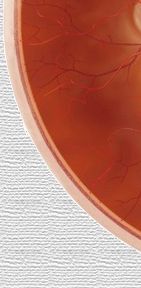

Cicatriz |

Nuevos vasos |

Hemorragias |